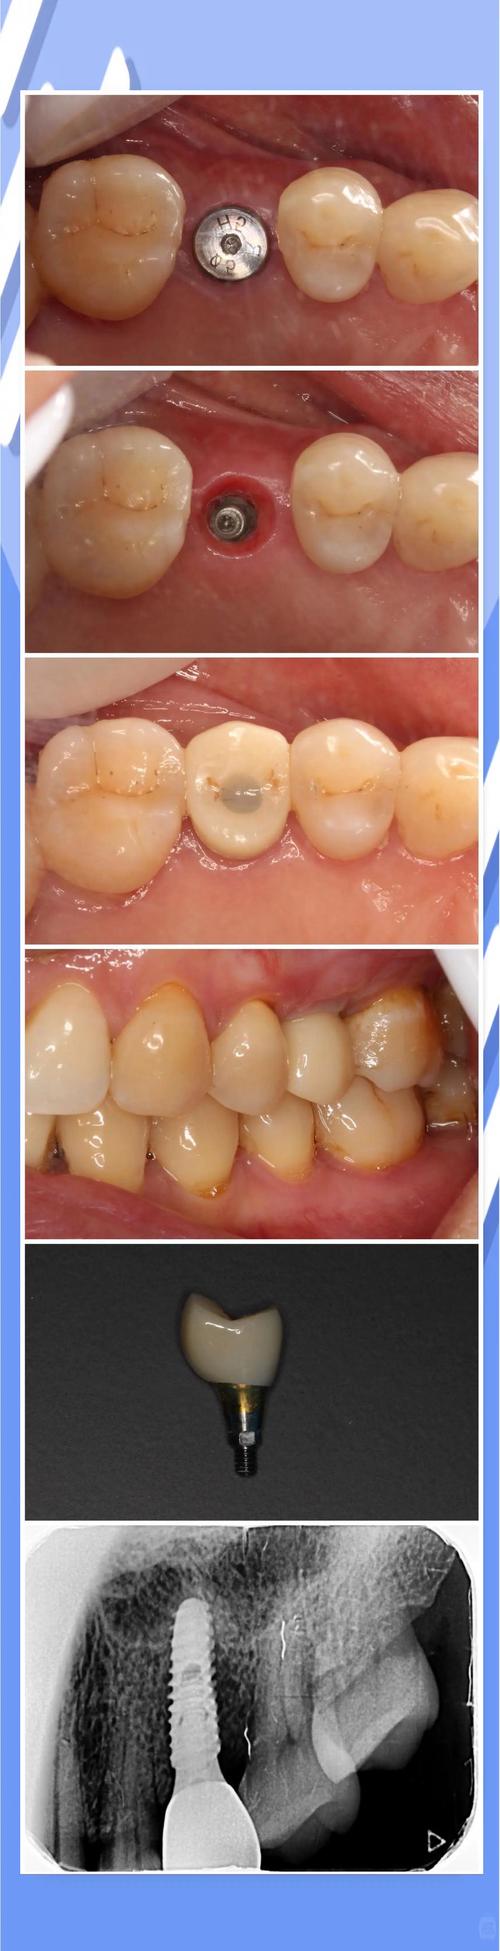

- 愈合帽: 在这个阶段,种植体上方通常会安装一个愈合帽,引导牙龈愈合形成良好的袖口形态,为后续修复做准备。

- 基台连接与牙冠修复: 确认骨结合牢固后,医生会进行二期手术(如果需要,有些系统是微创的),安装基台(连接种植体和牙冠的部分),然后取模制作并安装最终的牙冠。

- 骨结合形成: X光片检查显示种植体周围骨组织致密,种植体与骨之间没有透射影(暗线),骨小梁逐渐靠近种植体表面。

- 牙龈袖口健康: 围绕种植体颈部的牙龈组织健康、粉红、有弹性,形成良好的袖口形态,没有红肿、退缩或增生。